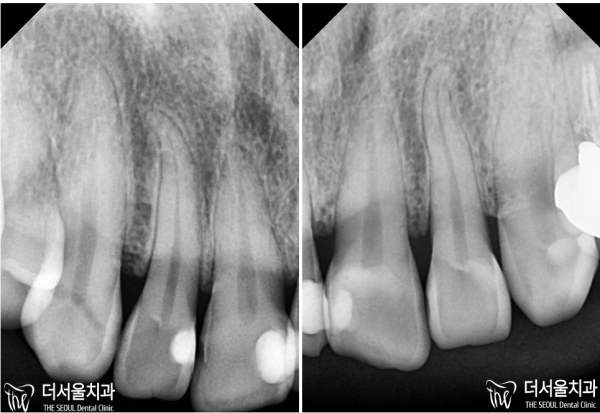

이 환자분은 치아 사이사이에 충치가 있었습니다.

즉, 인접면 충치인데요. 이 부분은 눈에 잘 안보이기 때문에

초기에 발견이 잘 안되는 특징이 있습니다.

평소 치실과 치간칫솔을 잘 사용하면 이러한 인접면충치의 위험을 많이 낮출 수 있다는것 잊지마세요!

This patient had a cavity between his teeth.

In other words, it's a cavity on the adjacent side. You can't really see this part

There is a feature that is difficult to detect in the early stages.

Don't forget that the usual good use of floss and interdental brushes can reduce the risk of these adjacent surface teeth a lot!